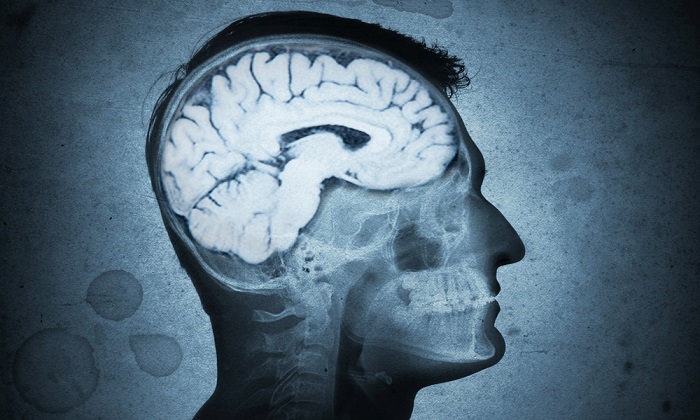

در شرایطی که پژوهش های پیشین حضور باکتری پی. ژنژیوالیس در نمونه های مغز بیماران مبتلا به آلزایمر را نشان داده اند، تیم پژوهشی از دانشگاه لوئیزویل و دانشگاه یاگیلونیا در کراکوف، لهستان به بررسی این مساله که آیا ممکن است باکتری در ابتلا به بیماری آلزایمر نقش داشته باشد، اقدام کردند.

پژوهشگران نمونه های مغز از بیماران مبتلا و غیر مبتلا به بیماری آلزایمر که در زمان مرگ تقریبا سنی مشابه داشتند را مقایسه کردند. آنها دریافتند که پی. ژنژیوالیس در نمونه های مغز بیماران مبتلا به بیماری آلزایمر بسیار بیشتر بوده است.

از این رو، پژوهشگران پژوهش خود را به سطحی جدید ارتقا دادند. با آزمایش روی موش ها، آنها دریافتند که پی. ژنژیوالیس می تواند از دهان به مغز سفر کرده و موجب مشکلات شناختی شود.